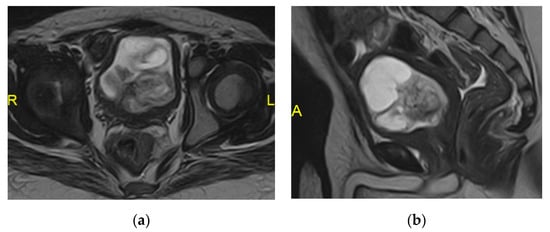

2.15. Acute Bacterial Prostatitis and Prostatic Abscess

- Ren, J.; Huang, X.; Wang, H.; Liu, H.; Ren, F.; Zhang, Z.; Yang, Y.; Yin, H.; Huan, Y. Prostatic abscess and seminal vesicle abscess: MRI findings and quantitative analysis of apparent diffusion coefficient values. Radiol. Infect. Dis. 2015, 2, 27–32. [Google Scholar] [CrossRef]

| Prostatic abscess | Non enhancing fluid collection with peripheral or septal enhancement and non-enhancing central fluid. Possible extraprostatic extension |